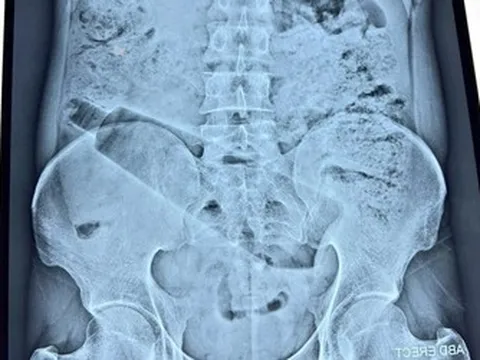

Tháng 1/2026 bệnh nhân đến Bệnh viện đa khoa Hoè Nhai thăm khám. Trong quá trình thăm khám, BS.Minh Nghĩa phát hiện túi ngực bên trái đã vỡ, tràn xung quanh khoang ngực.

Bác sĩ và ê-kíp đã tiến hành phẫu thuật tháo túi, rửa sạch khoang ngực và tiến hành đặt đòng túi ngực khác cho bệnh nhân.

Bác sĩ Nghĩa chỉ định cho bệnh nhân dùng thêm kháng sinh sau khi ra viện. Sau khi tái khám 14 ngày, nữ bệnh nhân hoàn toàn ổn định và hài lòng về kết quả hiện tại.